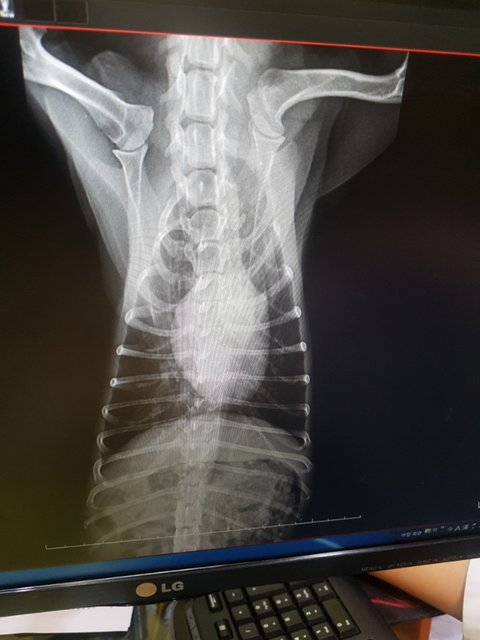

뇌압력이 높고 신경증상을 보이고 있습니다

귀안쪽 출혈이 있었고 폐쪽에도 사고충격으로 출혈이 조금 보이고 있다고 합니다

2~3일 뇌압을 낮추어보고 안내려가면 CT나 MRI를 찍어보자고 하십니다ㅜ.ㅜ